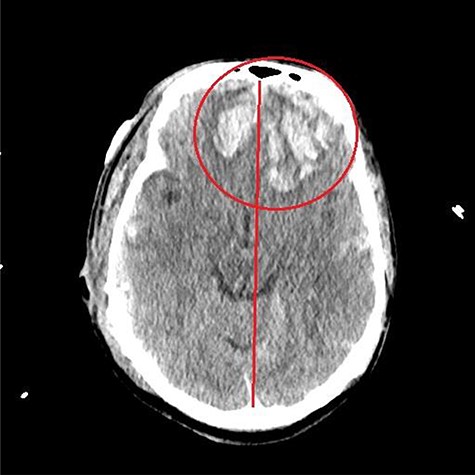

A 59-year-old male was found in the street with a head laceration. He was brought to the trauma bay as a pedestrian struck trauma patient with a prehospital GCS of 3. On arrival, his GCS was 11 (E3, V2, M6). An expanding neck hematoma was seen on exam. CT scan revealed scattered bilateral frontal contusions with hemorrhage in right basal ganglia, small bilateral acute SDH without significant mass effect, minimally displaced right temporal/occipital skull fracture and right-sided rib fractures 1–7 (flail chest) with hemopneumothorax (Fig. 1).

He was paralyzed, intubated and taken emergently to the OR due to nonresponsive hypovolemic shock. A right frontal ICP monitor was placed in the operating room while he was undergoing an emergency thoracotomy. Intraoperative ICP was in the 40s, and thus the patient was taken directly from the operating room to CT scan which showed enlargement of bilateral contusions, left greater than right, for which he was taken emergently to the operating room for a left hemicraniectomy (Figs 2 and 3).

CT head post thoracotomy with expansion of contusion with shift.